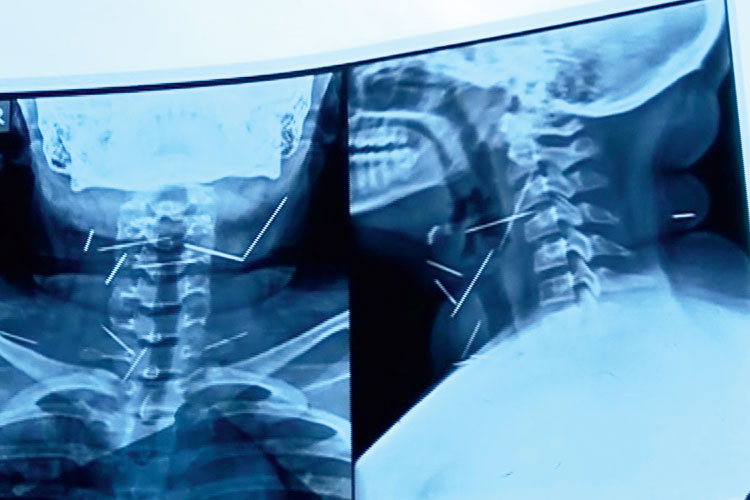

গত জুলাইয়ে কৃষ্ণনগর নরেন্দ্রনগর অক্ষয় বিদ্যাপীঠের অষ্টম শ্রেণির পড়ুয়া অপরূপাকে ন’টি সুচবিদ্ধ অবস্থায় কলকাতার নীলরতন সরকার হাসপাতালে ভর্তি করানো হয়। চিকিৎসকেরা প্রায় চার ঘণ্টার চেষ্টায় অস্ত্রোপচার করে তার গলার ভিতর থেকে ন’টি সুচ বার করেন। কিন্তু কী করে এতগুলি সুচ ওই কিশোরীর গলায় ঢুকল, অপরূপার বাবা-মা সেই বিষয়ে তখন কিছুই জানাননি। তবে নীলরতনের চিকিৎসকেরা জানিয়েছিলেন, ওই কিশোরীর গলার যে-জায়গা থেকে সুচগুলি বেরিয়েছে, তাতে এটা স্পষ্ট যে, সে নিজে সেগুলি ঢোকায়নি।

অপরূপারই গলায় ফুটে ছিল ন’টি সুচ। —নিজস্ব চিত্র